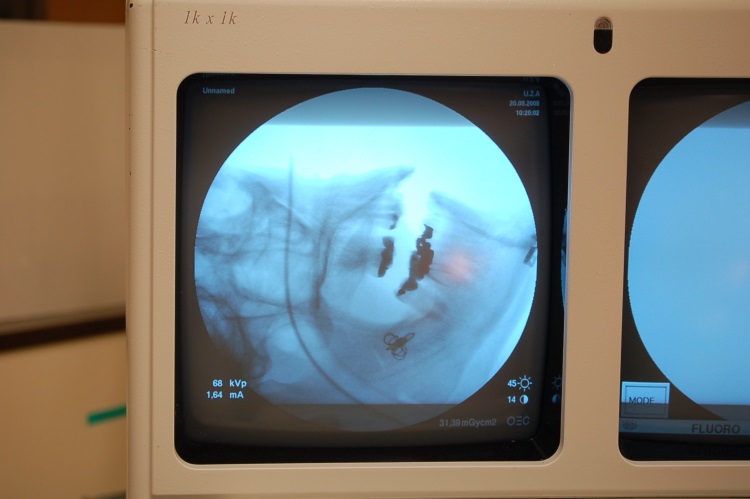

Antwerpy, Belgie